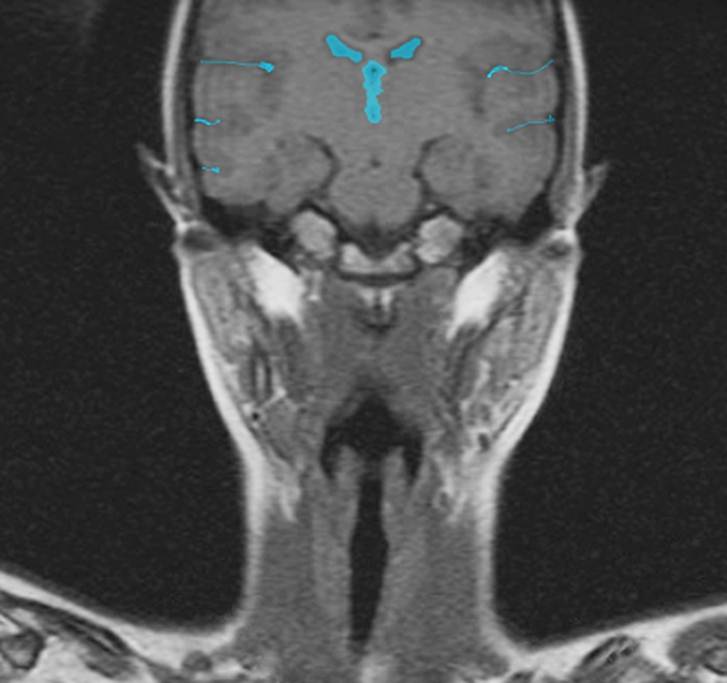

CT: Brain Atrophy

10 Years-Normal Gyri             65 Years-Enlarged Gyri